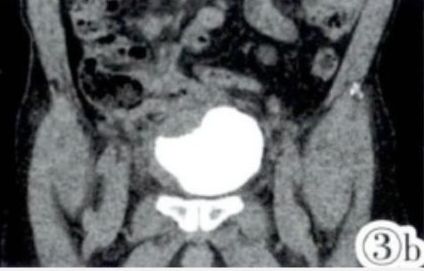

图3a,3b CTU重组示受累回肠与膀胱紧密相连,膀胱右侧壁、膀胱底受压变形。